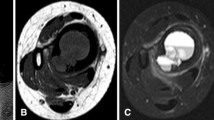

Acute osteomyelitis radiographic findings (a) can be aggressive and similar to those of Ewing’s sarcoma (permeating lesion with periosteal reaction, arrow in a). MRI however shows diffuse soft-tissue swelling, with no well-defined soft tissue mass (b axial T1WI; c sagittal T1WI; d contrast-enhanced T1WI)